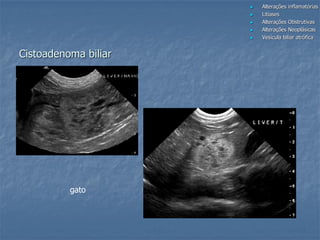

Cistoadenoma biliar

gato

felino

canino